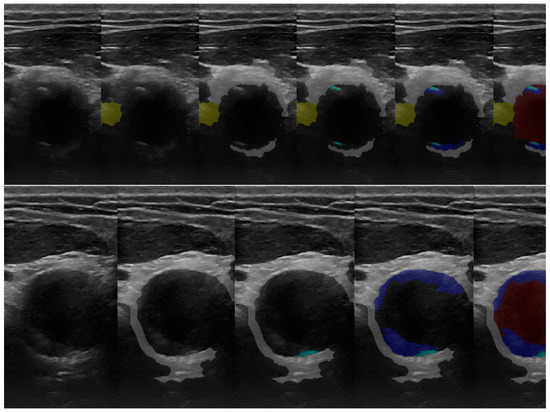

3.1. 2D Automatic Segmentation

3.1.1. Automatic Segmentation Results Compared with the Gold Standard (Operator’s Segmentation)

3.1.2. Automatic Segmentation (MultiRes U-Net) Training Results Metrics